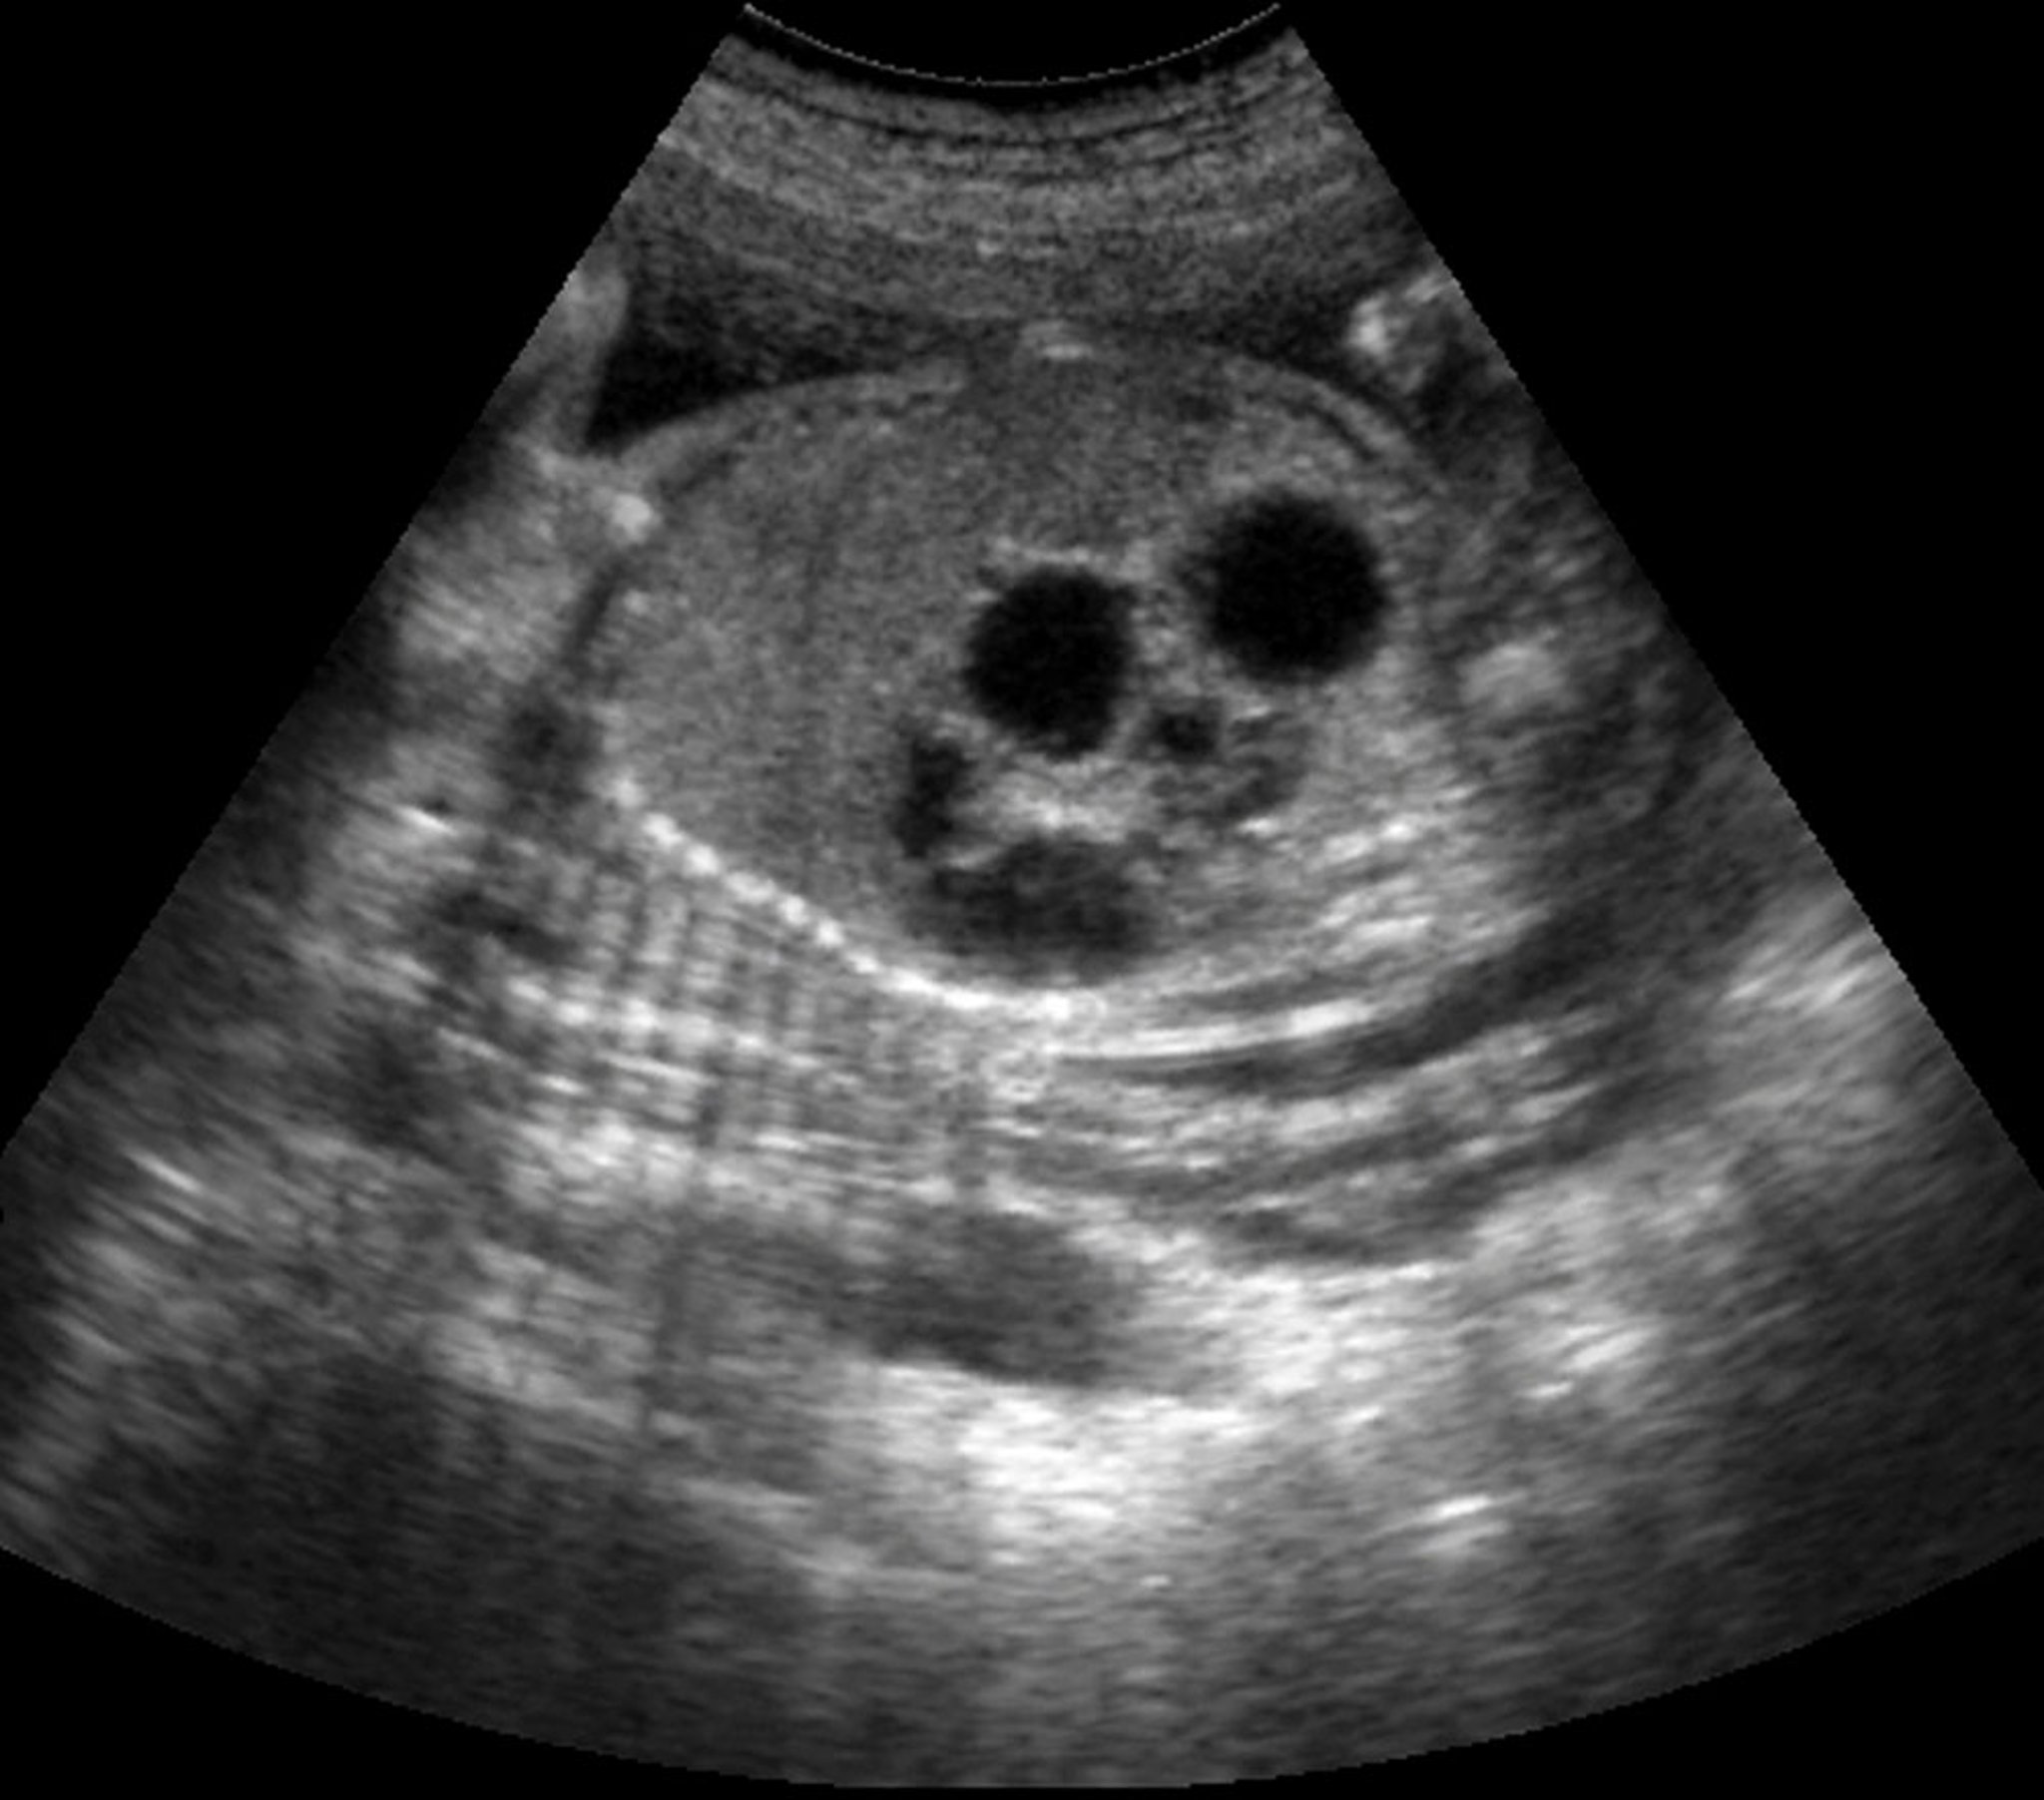

Chẩn đoán teo tá tràng được nghi ngờ trước khi sinh nếu có tình trạng đa ối và/hoặc dạ dày bị giãn. Siêu âm trước khi sinh có thể phát hiện dấu hiệu bong bóng đôi (bong bóng dạ dày lớn và bong bóng tá tràng gần nhỏ hơn) ở 80% số trường hợp (2).

Siêu âm này cho thấy dấu hiệu bong bóng đôi ở thai nhi bị teo tá tràng.

BÁC SĨ NAJEEB LAYYOUS/THƯ VIỆN HÌNH ẢNH KHOA HỌC